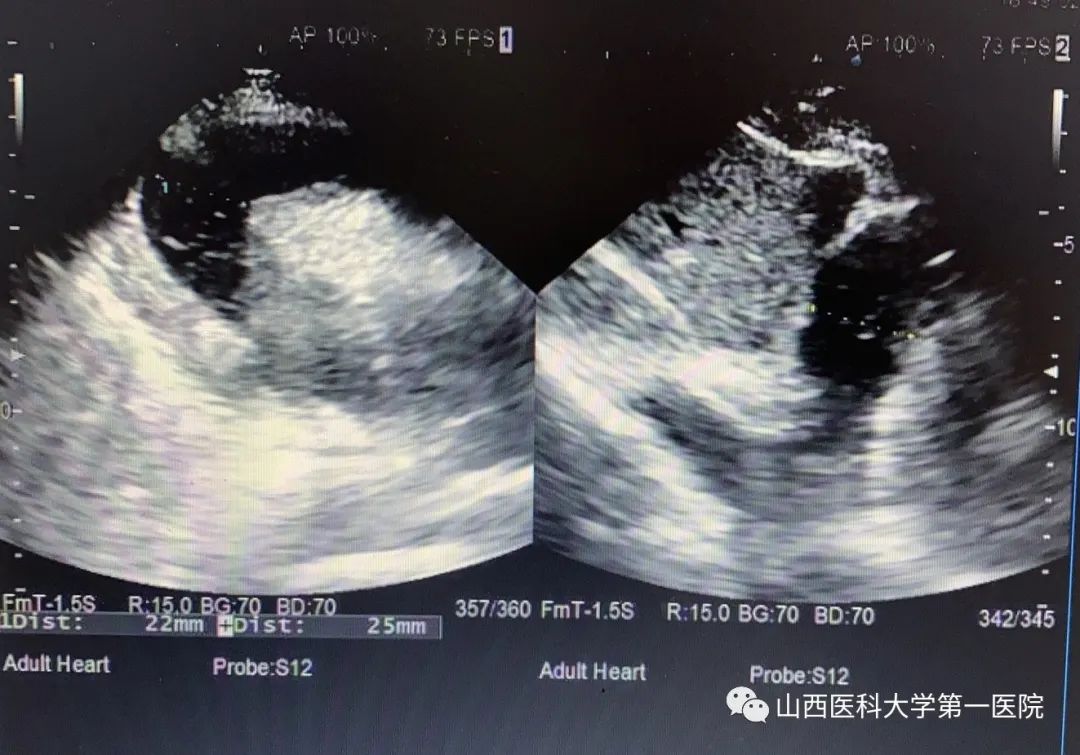

2023年11月1日16时58分,河曲县人民医院急诊“120”车接回一例车祸外伤患者。该患者自驾车时发生车祸,来院时意识模糊,烦躁明显,不能描述具体受伤过程。经检查,患者面色、口唇青紫,胸部皮肤大面积紫绀,呼吸急促,血氧饱和度46%,呼吸25次/分钟,心率126次/分钟,血压125/100mmHg。急诊科医护团队迅速评估伤情并展开急救:高流量吸氧、建立静脉通路、严密心电监护。患者表现为严重的低氧血症,氧疗后氧饱和度仅上升至60%左右,皮肤仍紫绀,极度烦躁不安。紧急行头、胸、腹、脊柱等部位CT检查。张嘉利医师获得CT影像资料后发现患者存在大量心包积液,结合患者症状,考虑“创伤性心脏损伤致心包填塞”,立即制定心包穿刺术抢救计划,并协调人员与物资。在B超精准定位下,张嘉利医师紧急为患者行床旁心包穿刺置管引流术,术中穿刺抽吸出100ml暗红色血性液。患者低氧血症的症状随即明显减轻,呼吸逐渐平稳,心率逐渐降至正常,血氧饱和度上升至90%以上。后留置引流管持续引流。术后,患者转入急诊ICU密切监护。至11月2日8时,心包穿刺引流管又引流出260ml心包内积血。患者生命体征平稳,对答准确,自诉无明显不适。11月3日,行B超复查后,顺利拔除引流管。